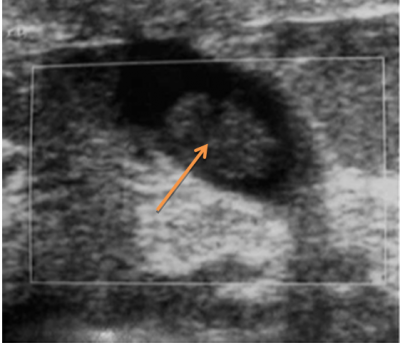

האבחנה מתבססת על הסיפור הקליני והבדיקה. ב-US אפשר להדגים צינורות מורחבים כביטוי לדוקטאקטזיה או אף לראות את הפפילומה (תצלום 16.12).